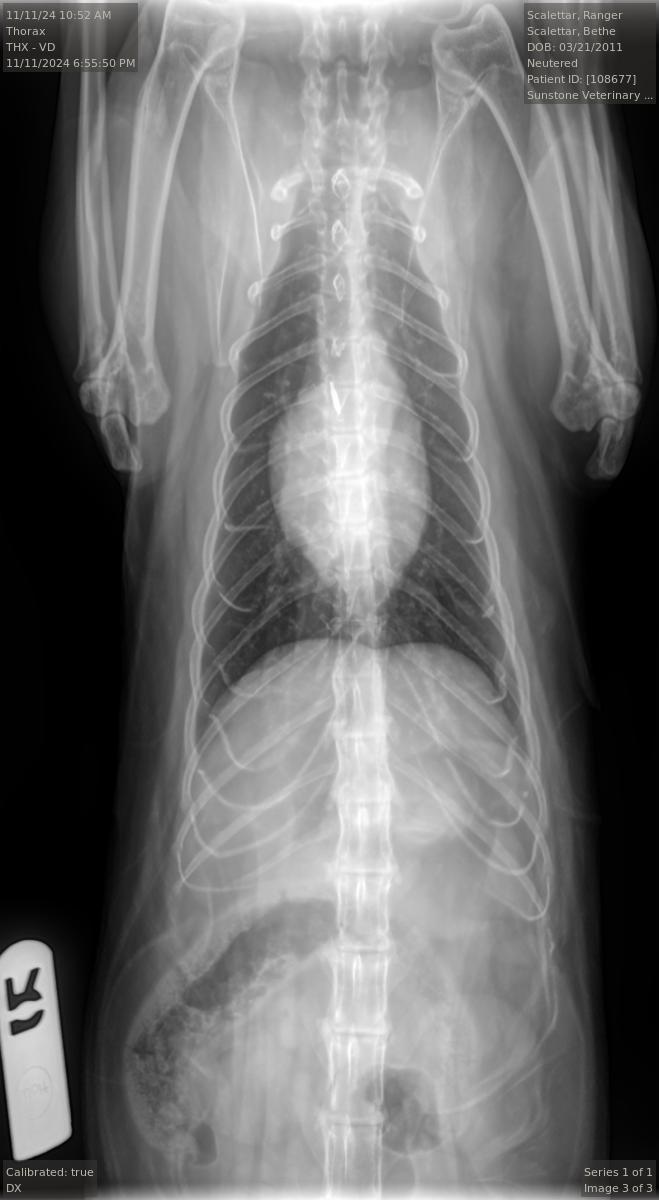

Veterinary diagnostic radiographic studies of the thorax and/or abdomen typically include at

least two projections: (1) a right (R) or left (L) lateral view, and (2) a ventrodorsal (VD) or

dorsoventral (DV) view. Right and left lateral views are taken with the animal lying on its right

(R) or left (L) side, respectively. Ventrodorsal and dorsoventral views are taken with the animal

lying on its back (VD) or stomach (DV), respectively. Radiopaque markers (e.g., “L” and “R”) are

placed near the animal to distinguish the views.

Projection radiographs lack depth information because the intensity of each point in the image

is a superposition of all structures along a given straight-line X-ray trajectory through the body.

However, by taking images along at least two orthogonal directions (e.g., R or L AND VD or DV),

the veterinarian can obtain three-dimensional information from the two-dimensional images.

For example, the pairs of superimposed ribs visible in the accompanying L and R radiographs

are visible as separate left and right ribs in the VD view. Taking both L and R views, or both VD

and DV views, can yield additional information.

The radiologist stated that the Ranger's radiographs were largely normal for an older cat. In

particular, they show arthritic changes in both elbows and the middle back. However, the

images did not show any abnormalities in the lungs and only mild, if any, enlargement of the

heart. Overall, these were good results.